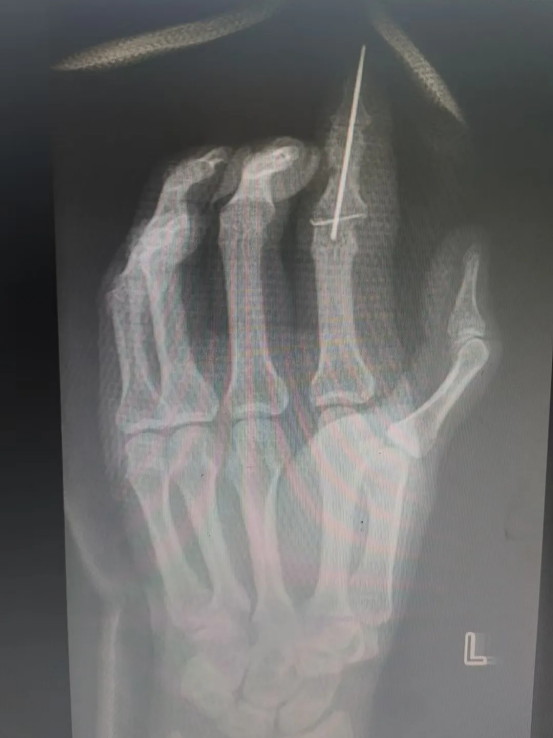

飞来横祸|机器绞伤,手指多段离断

吴女士(化名)在工作时不慎被机器绞伤左手,当即感到示指剧痛、出血并活动受限。家属迅速将其送至重庆郭昌毕中医骨伤医院急诊科。经检查并结合X光片,诊断为“左手示指多层面离断伤”,伴血管、神经、肌腱严重损伤,伤情复杂严峻。

术前摄片